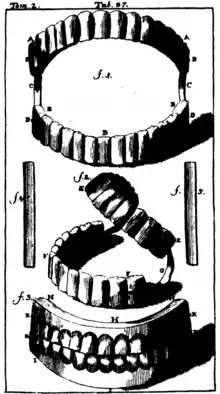

As early as the 7th century BC, Etruscans in northern Italy made partial dentures out of human or other animal teeth fastened together with gold bands.[14] The Romans had likely borrowed this technique by the 5th century BC.[14]

Wooden full dentures were invented in Japan around the early 16th century.[13] Softened beeswax was inserted into the patient's mouth to create an impression, which was then filled with harder bees wax. Wooden dentures were then meticulously carved based on that model. The earliest of these dentures were entirely wooden, but later versions used natural human teeth or sculpted pagodite, ivory, or animal horn for the teeth. These dentures were built with a broad base, exploiting the principles of adhesion to stay in place. This was an advanced technique for the era; it would not be replicated in the West until the late 18th century. Wooden dentures continued to be used in Japan until the Opening of Japan to the West in the 19th century.[13]

In 1728, Pierre Fauchard described the construction of dentures using a metal frame and teeth sculpted from animal bone.[13] The first porcelain dentures were made around 1770 by Alexis Duchâteau. In 1791, the first British patent was granted to Nicholas Dubois De Chemant, previous assistant to Duchateau, for "De Chemant's Specification":